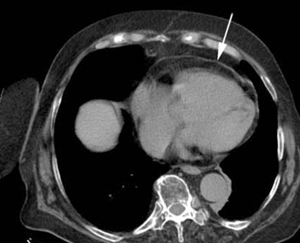

Se solicitó ecocardiografía transtorácica que mostró: fracción de eyección del ventrículo izquierdo (FEVI) 55%, ventrículo izquierdo con hipertrofia leve, hipoquinesia biventricular difusa, dilatación leve de aorta ascendente, aurícula izquierda moderadamente dilatada, engrosamiento pericárdico con probable derrame y colapso parcial de la aurícula derecha. Se solicitó tomografía de tórax (TC) sin contraste (figura 1) y (figura 2) que mostró una imagen típica de lipoma pericárdico, de 48 por 33 mm, que provocaba colapso de la aurícula derecha, considerándose la causa del taponamiento a baja presión. La angiografía coronaria no evidenció lesiones estenóticas significativas.